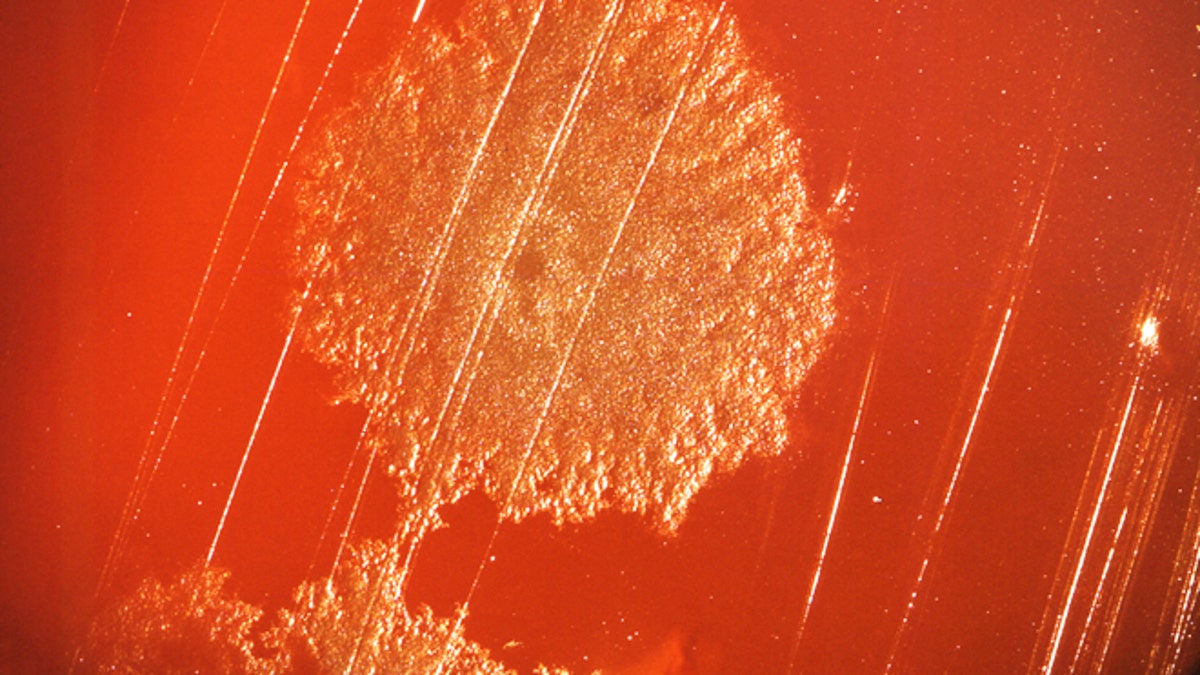

A colony of Clostridium sp. bacteria, which had been grown on a plate over a 48-hour time period. (CDC)